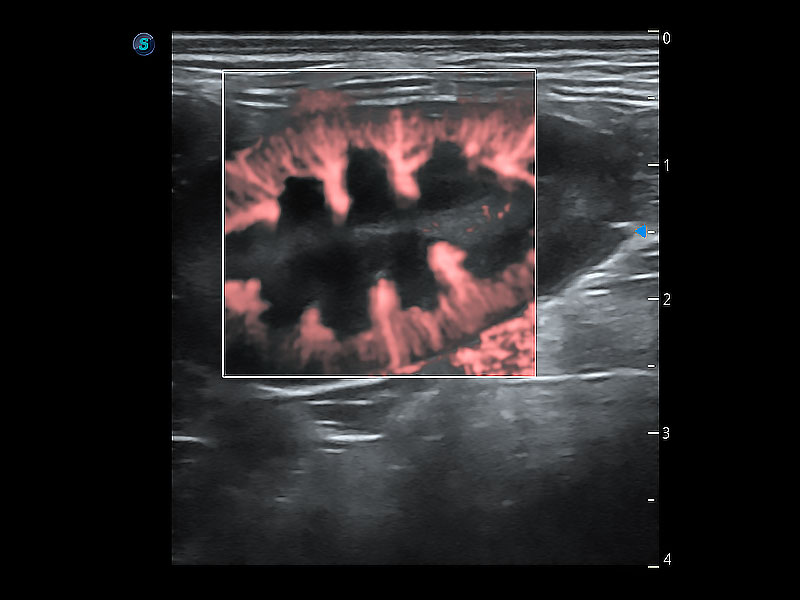

極大提升超低速微細(xì)血流的檢出能力,同時更精準(zhǔn)地濾除軟組織和超聲信號,為獸用醫(yī)生提供以往無法通過常規(guī)血流獲得的疾病診斷信息。

在傳統(tǒng)二維血流成像的基礎(chǔ)上,呈現(xiàn)血流的立體感,具有動感的生命力之美。即便是微小的血管也能輕松應(yīng)對,提高了血流的視覺敏感性。

非線性融合造影成像充分利用諧波和基波信號,為難以觀察的血流進(jìn)行增強(qiáng)顯像??捎糜诰€陣、凸陣、微凸陣、相控陣探頭。